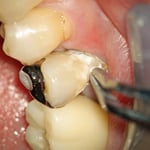

虫歯を丁寧に除去すると、かなり深い場所まで虫歯があることがわかります。虫歯を完全に除去し、接着操作のために酸で歯面を処理します。特殊なセメントをキャリアし、象牙質に緊密な絆創膏を貼ります。(周囲の象牙質の耐酸性が向上する効果もあります)この症例の場合、欠損部にグラスファイバーのポストをたてました。(縦方向の力に耐えるため)プラスティックを充填して完了です。

型採りの時も顕微鏡を使っています。